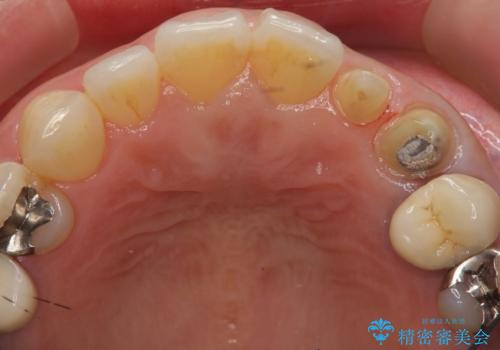

- 左上の前歯が小さく左右対称ではないのと、保険の前歯の被せ物のやりかえを希望して来院。

小さい前歯は、反対側と合わせた形にしました。

被せ物だけやりかえており、患者様のご希望もあり、根の治療や土台(コア)のやりかえは行なっていません。